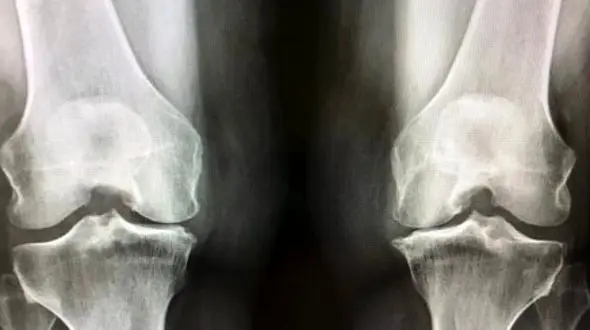

رکنا: آرتروز زانو با این نشانه ها و علائم بروز پیدا می کند.